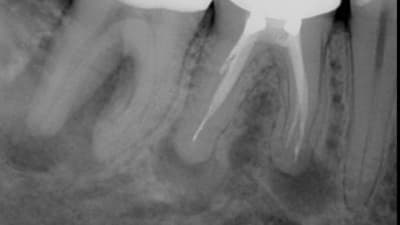

Clinical Briefs CAD | CAM Prosthodontics Fabricating New Dentures From Existing Ones By Rami Ammoun, DDS September 01, 2021 6 min read